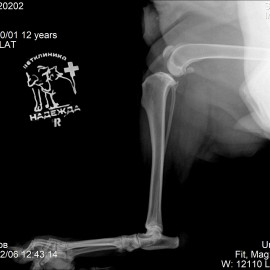

Наш пациент собака возрастом 13 лет по кличке линда. Обратились в нашу клинику с жалобами на хромоту на заднюю правую лапу. После проведенных исследований был поставлен диагноз - разрыв передней крестообразной связки правого коленного сустава.

Снимок 1 до операции.